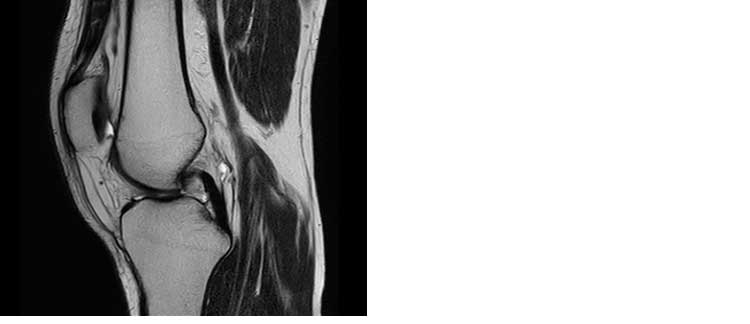

L’esame permette una corretta valutazione delle strutture scheletriche, delle componenti muscolari e tendinee per una corretta valutazione delle patologie articolari.